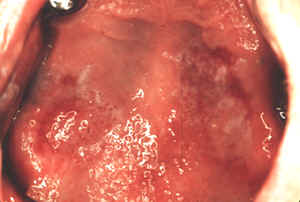

| El paladar es un sitio raro pero puede ser involucrado en los pacientes con enfermedad severa. |

| Esta mujer padece una considerable incomodidad

devido a un liquen erosivo.

El paciente también tiene diabetes mellitus, una enfermedad asociada a menudo con el

liquen plano. Estudios en un grupo de pacientes con liquen

plano revelan que un 30% tienen alterada la curva de tolerancia a

la glucosa.